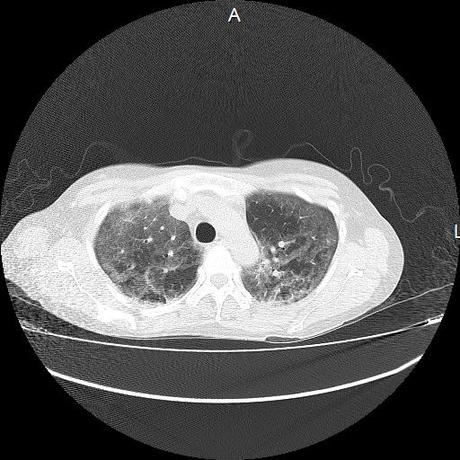

El parénquima pulmonar con areas parcheadas difusas en vidrio despulido combinadas con otras areas hipodensas de baja atenuación debidas a atrapamiento aéreo y engrosamiento intersticial y zonas de fibrosis de predominio en lóbulos medios e inferiores de ambos pulmones.

- LOS HALLAZGOS PUEDEN ESTAR EN RELACIÓN A NEUMOPATIA INTERSTICIAL PROBABLE ETIOLOGIA HIPERSENSITIVA VS AUTOINMUNE/BACTERIANA/FUNGICA.